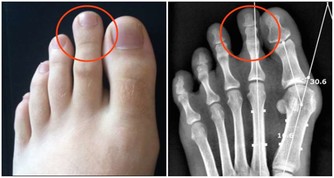

睡覺時要注意驅寒保暖,尤其是在冬天,不讓局部肌肉受寒。走路或運動時間不可過長,不能讓小腿過度疲勞。適當補鈣,尤其是正在發育期的青少年。但要在明確低鈣背後的真正原因後,再進行有針對性的治療,而不是一味補鈣。平足和其他身體構造的問題使一些人特別容易發生小腿抽筋,對於該人群,選擇合適的鞋是彌補的方法之一。